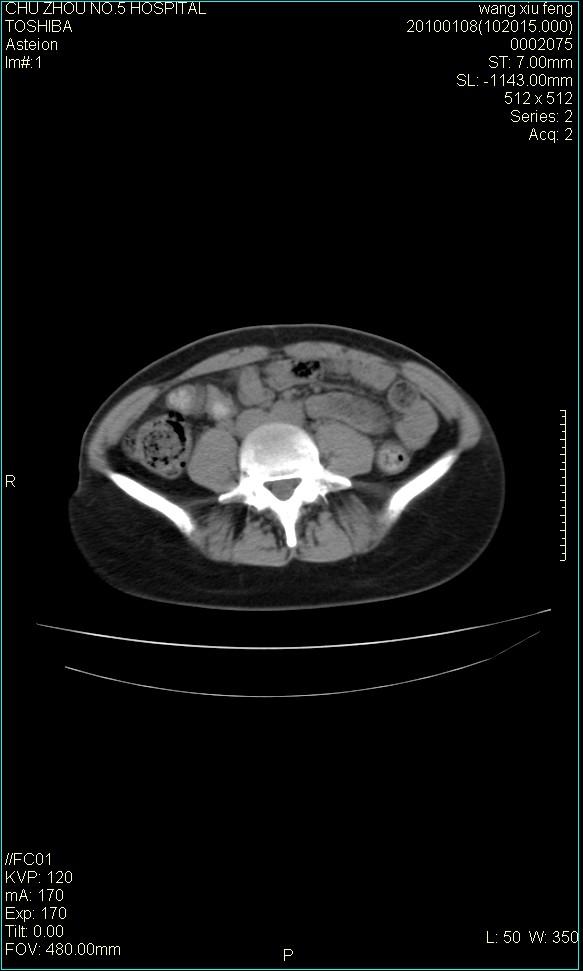

标题: CT24042:子宫右上方囊性包块,性质???? [打印本页]

标题: CT24042:子宫右上方囊性包块,性质????

f-41,左乳腺ca术后4年,b超示:子宫右上方囊性包块约5.5*3.4cm,前日行胸部ct平扫未见明显异常。